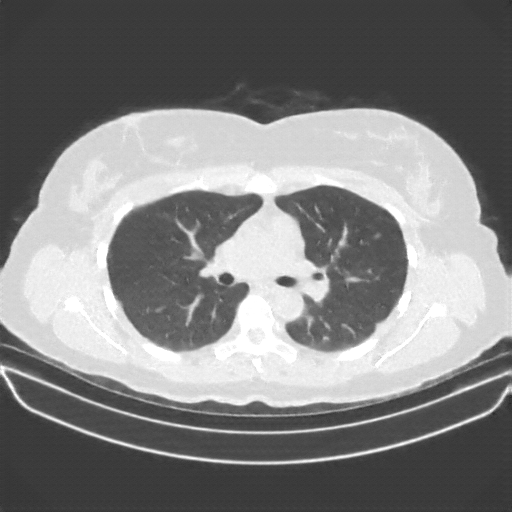

Generated VENOUS CT scan (A→B translation)

Lung window (WL -600, WW 1500 β†’ Low βˆ’1350, High +150)

Targeted Slice 70 - Lung Window Analysis (Generated vs Real Venous)

0.763

Lung SSIM

85.0

Lung RMSE

36.7

Lung MAE

Average Lung Window Metrics Across All Slices (170 slices) - Generated vs Real Venous

0.767

Lung SSIM (Avg)

89.5

Lung RMSE (Avg)

37.4

Lung MAE (Avg)